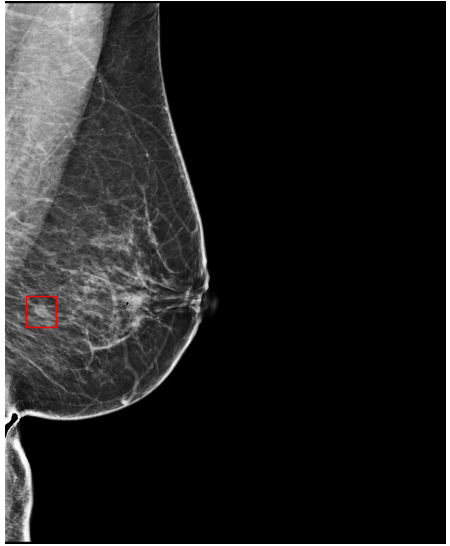

Refer to caption

(a) FeatAlign

(b) FeatAlignReg

(c) ImgFeatAlign/ImgAlign

(d) FeatAlign

(e) FeatAlignReg